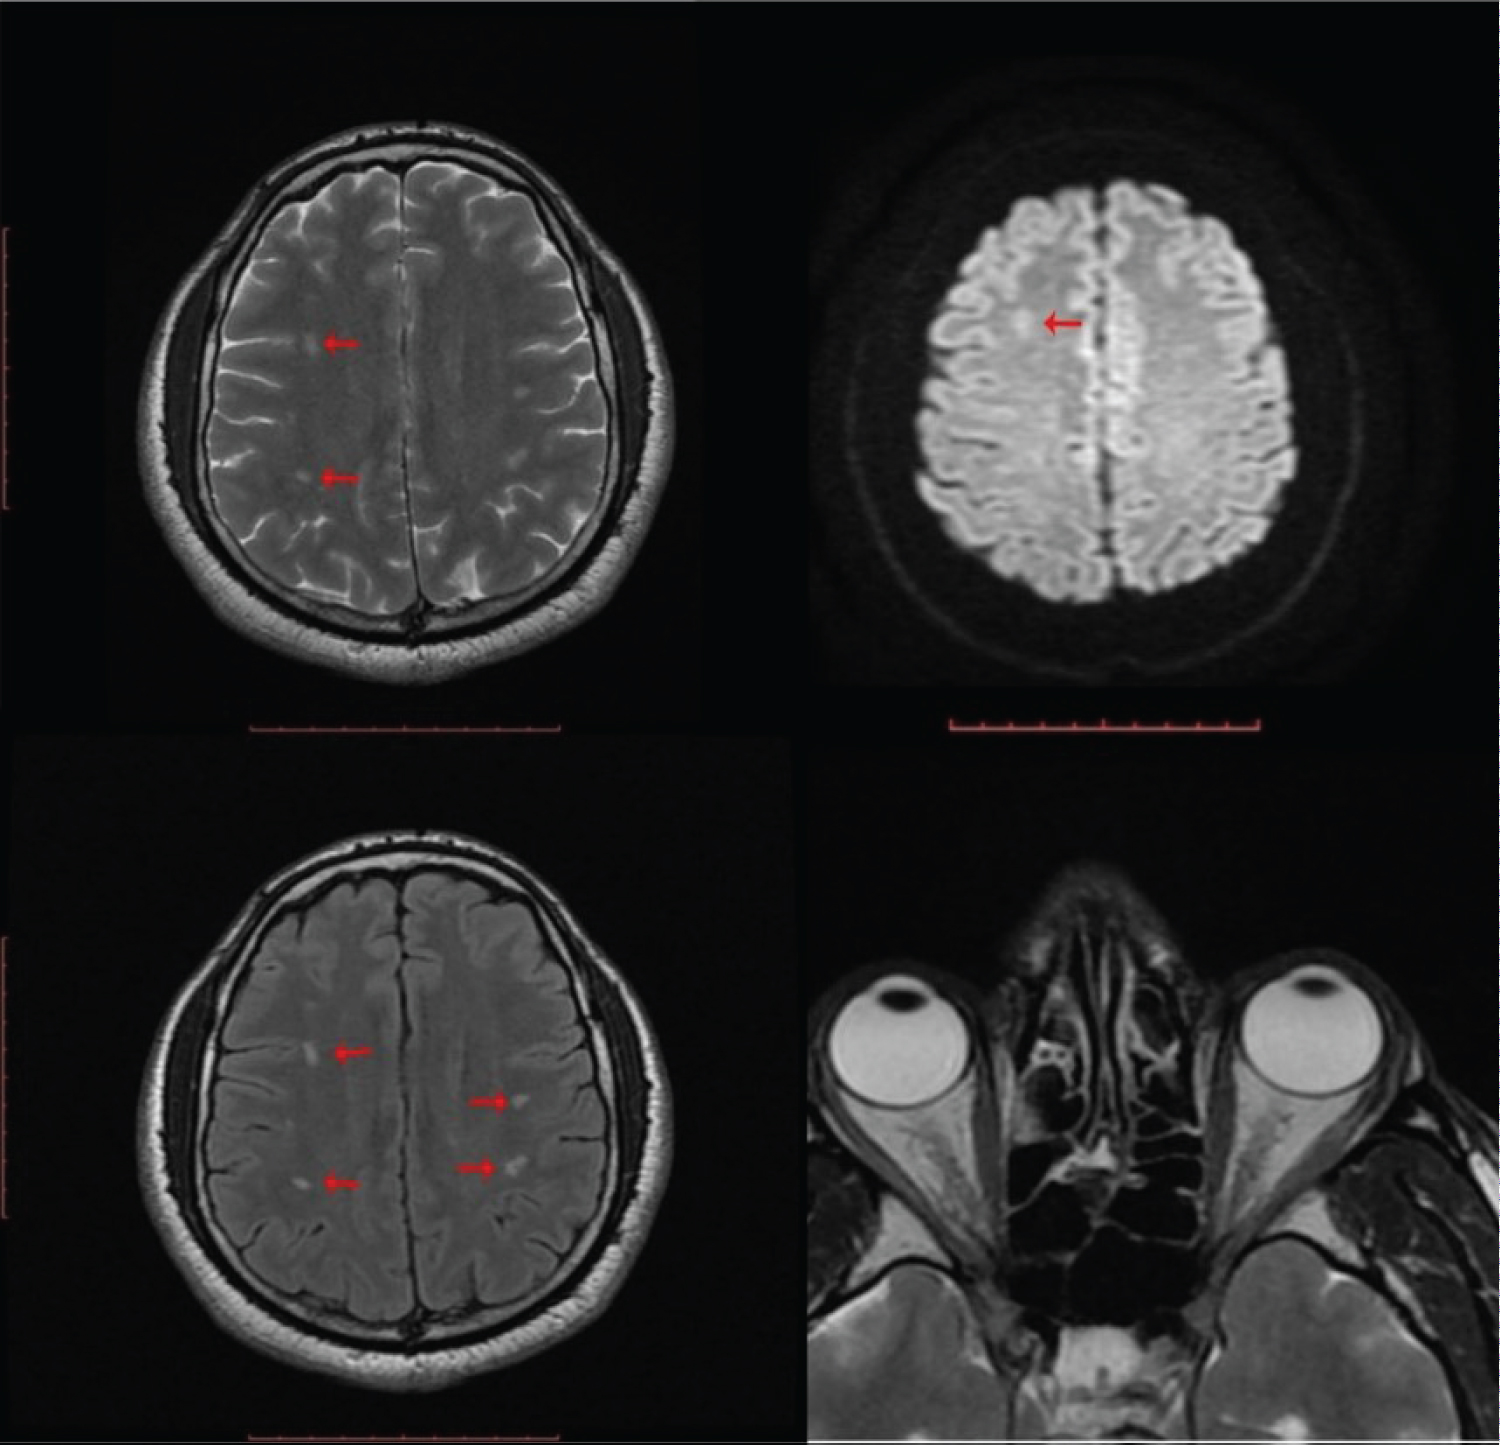

Optical coherence tomography showed bilateral thickening of the retinal and blurring of the disc margins consistent with optic disc edema. The disc edema distorted the anatomy of the optic disc which resulted in the erroneous estimation of the cup to disc ratio (CDR) of 0.92 × 0.96 in the right eye, see (Figure 3A). The edema in the left optic disc was less hence the accurate CDR of 0.22 × 0.23. The vessels were of normal volume and caliber bilaterally. Full blood count showed relative lymphocytosis and lipid profile showed dyslipidemia with an elevated total cholesterol of 248 mg/dl and low density lipoproteins (LDL) of 170 mg/dl, see (Table 1). Magnetic resonance imaging with T2 weighting obtained five weeks after the onset of symptoms showed multiple bilateral and asymmetrical small-sized T2/FLAIR deep white hyperintense lesions, predominantly in the centrum semiovale showing restricted diffusion with relatively high ADC values consistent with small vessel ischemia, see Figure 5.

Figure 5: Magnetic resonance imaging with T2 weighting obtained five weeks after the onset of symptoms showed multiple bilateral and asymmetrical small sized T2/FLAIR deep white hyperintense lesions, predominantly in the centrum semiovale. These lesions show restricted diffusion with relatively high ADC values- consistent with small vessel ischemia, indicated by the red arrows. View Figure 5

The mechanism by which CoVs affect the nervous system can be linked to their direct invasion of the tissues of the system with genetic materials passing through neuronal pathways such as the olfactory bulb, and blood circulation; although, the invasion of the SARS-CoV-2 virus through the blood is rare. High levels of D-dimer were found in patients with the critical SARS-CoV-2 viral infection and thus predisposing them to acute cerebrovascular diseases, this was found in 5.7% in a review of 214 COVID-19 patients carried out in Wuhan, China [13,14]. The multiple bilateral and asymmetrical small-sized T2/FLAIR deep white hyperintense lesions, predominantly in the centrum semiovale were due to a diffuse viral invasion of the brain tissues.